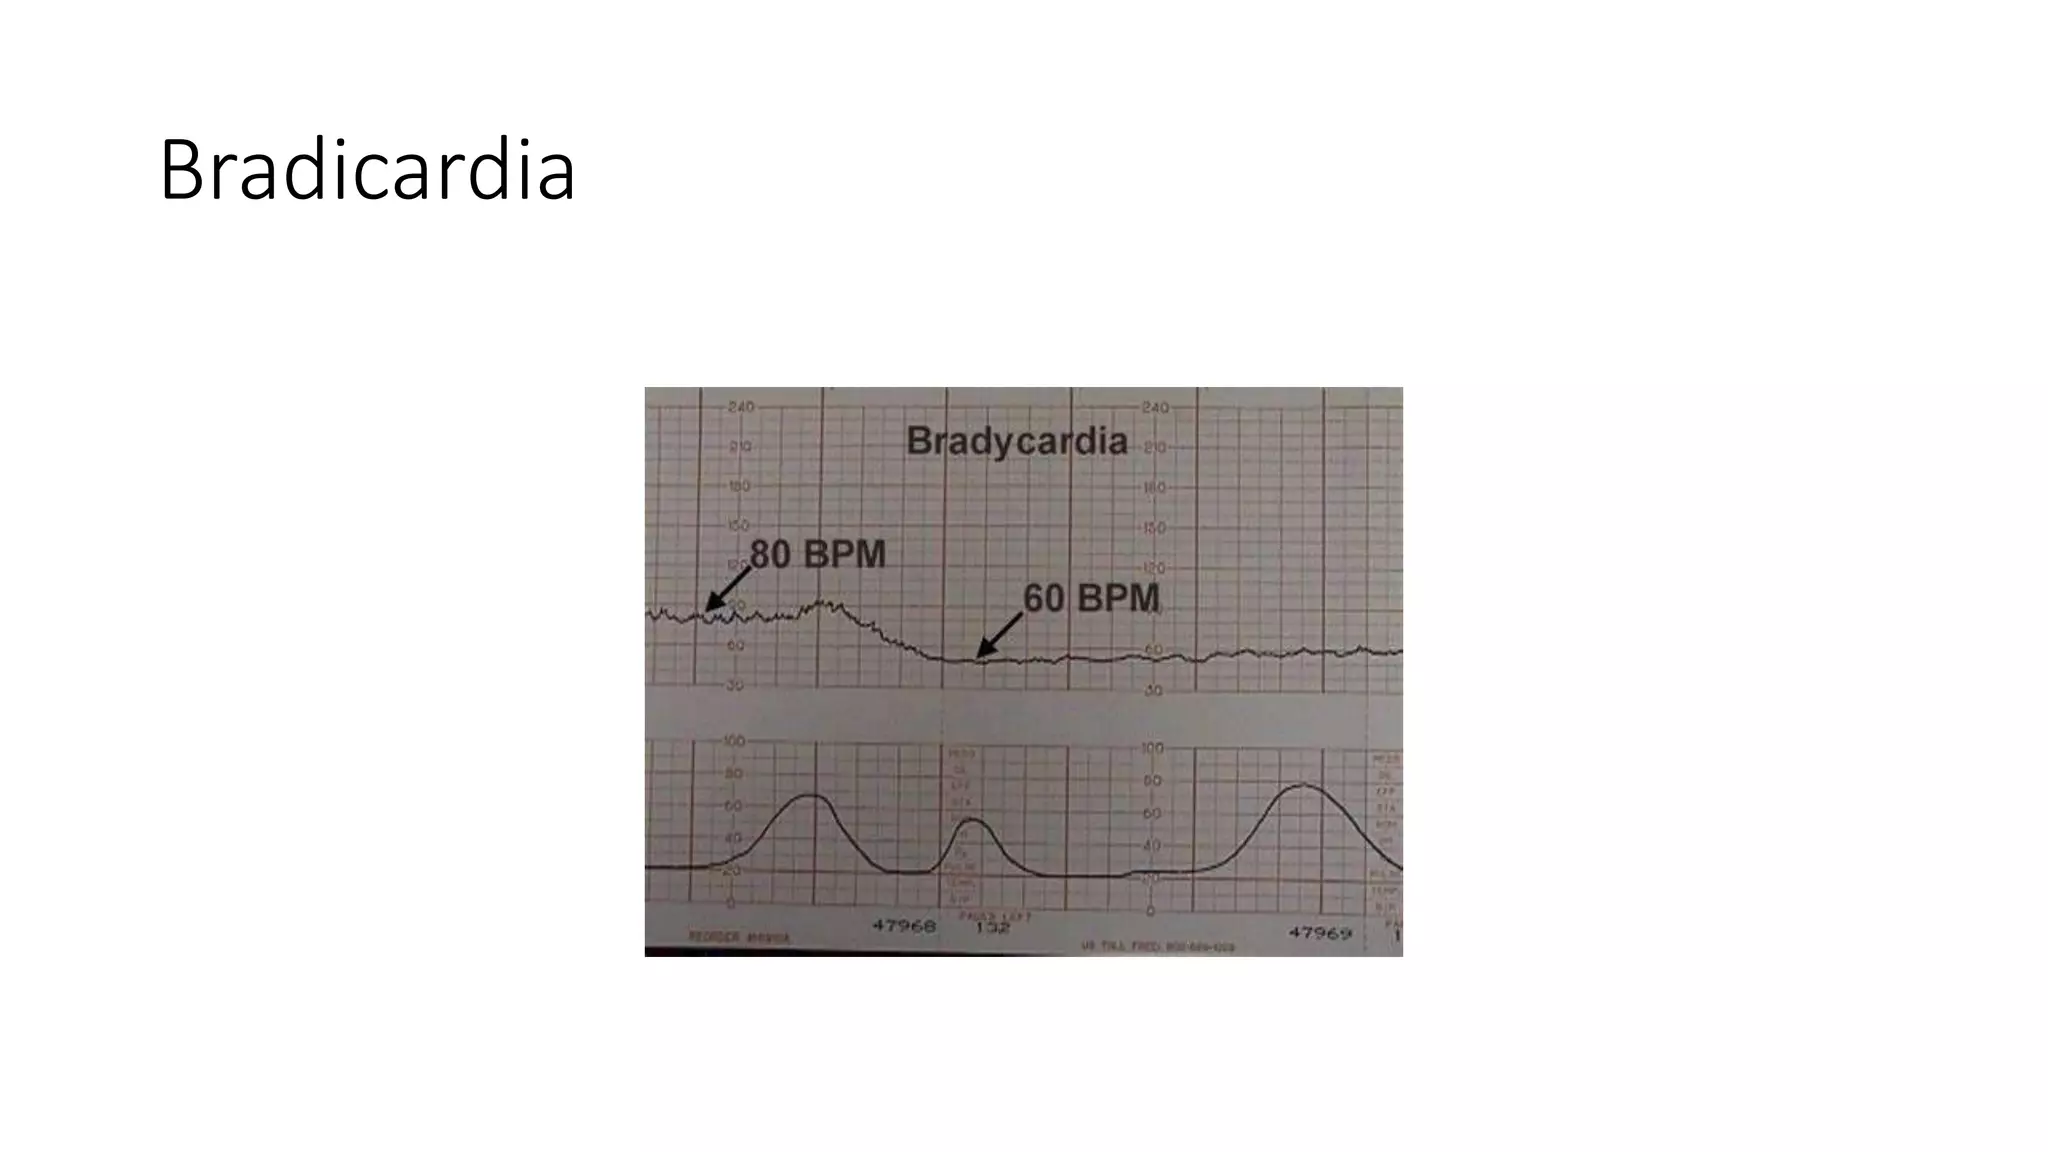

The document discusses key metrics for monitoring a baby's heart rate in utero, including the normal baseline rate of 100-160 bpm and variability. It also covers types of accelerations and decelerations that can occur, such as early or late, as well as bradycardia, which is an abnormally slow heart rate.